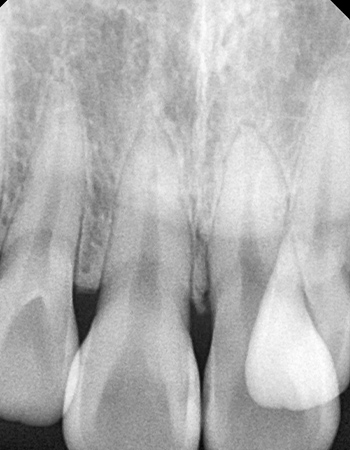

CASE 02

확장 전

확장 후